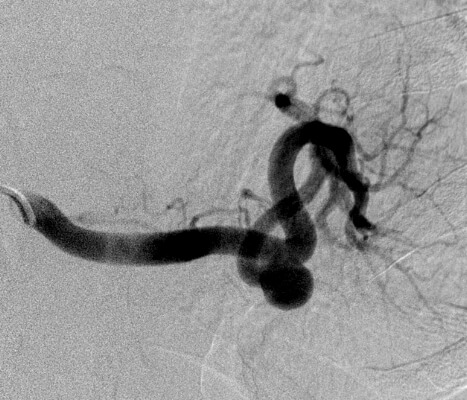

36 year old female with no significant past medical history who presents to the ED with right lower quadrant pain who underwent a CT scan for further evaluation.

36 year old female with no significant past medical history who presents to the ED with right lower quadrant pain who underwent a CT scan for further evaluation.